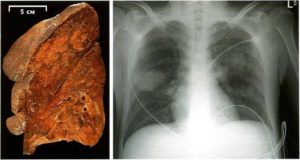

Инфекционно-воспалительное заболевание легких, в ходе которого ткани парного органа подвергаются дистрофическим изменениям. Наблюдается отек, боли за грудиной (сильные), тяжелые нарушения дыхания, одышка, удушье, свистящие хрипы при дыхании у взрослого.

Наиболее выражена клиническая картина при двухстороннем поражении. Это наиболее опасная форма недуга.

Провоцируется микробактерией туберкулеза, также известной как палочка Коха. Речь идет о сложном и комплексном недуге, способном привести к летальному исходу. На поздних стадиях болезнь приводит к расплаву легочной ткани.

Характеризуется недуг болями за грудиной, кашлем, кровохарканием, резкой утратой массы тела, одышкой, удушьем, влажными хрипами в легких. Без лечения легкие разрушаются буквально за несколько лет. Более того, возбудитель туберкулеза имеет свойство транспортироваться в иные ткани и органы, формирую очаги вторичного поражения.